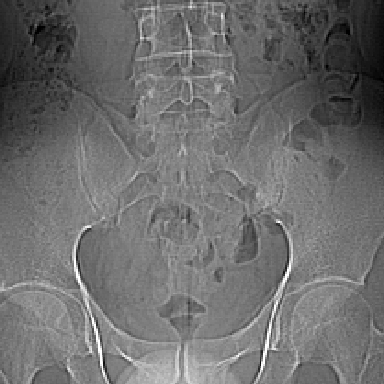

m 30 腰背部不适半年; 清晨时僵硬; 活动症状有所改善

双侧骶髂关节下2/3关节面模糊,毛糙,可见小囊状骨质破坏区.支持强直性脊柱炎.

强直性脊柱炎的早期改变!不仅表现为双侧骶髂关节,第5腰椎与骶椎间的关节突关节也有类似改变。

双侧骶髂关节下2/3关节面模糊,毛糙,髂骨侧可见小囊状骨质破坏区,骶髂关节间隙增宽(软骨破坏期)。支持早期强直性脊柱炎。

双侧骶髂关节下2/3关节面模糊、毛糙,可见小囊状骨质破坏区,呈虫咬状改变,周围可见增生硬化.支持强直性脊柱炎早期表现.

双侧骶髂关节髂骨面硬化,毛糙,小囊变,属于早期强直性脊柱炎